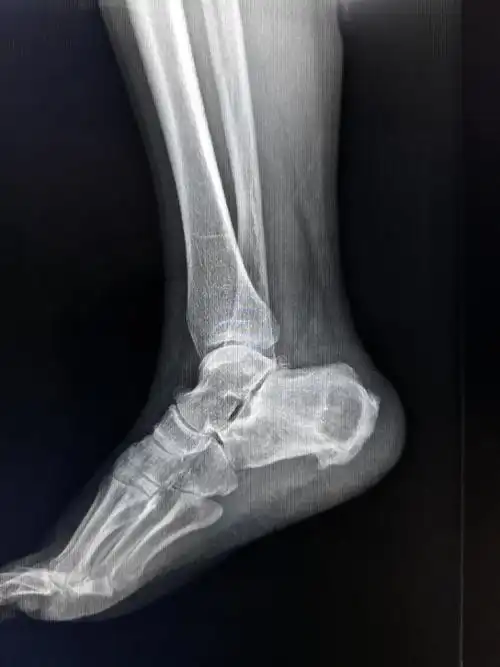

典型x线片

右足跟骨骨折